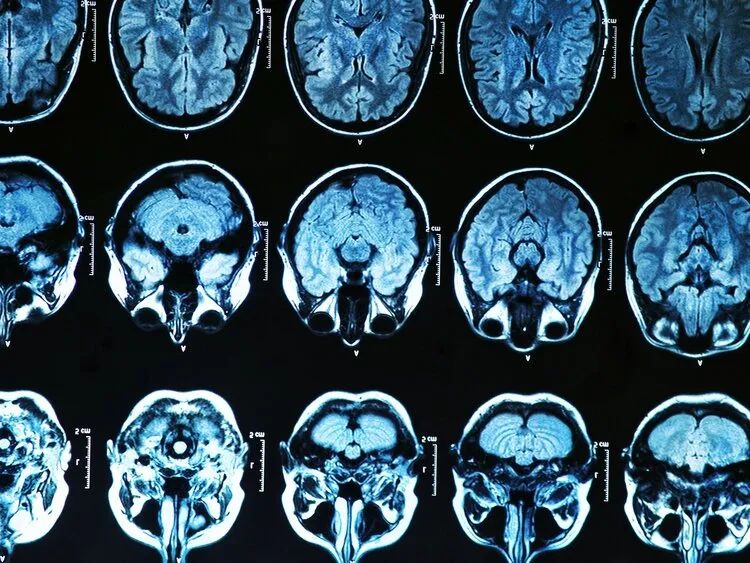

脑萎缩是指各种原因引起的 脑体积变小,细胞数目变少的现象 。脑萎缩只能在CT或MIRI检查时被发现,因此,脑萎缩也是许多疾病的神经影像学表现。 严格来说,脑萎缩并不是一种疾病,而是一种症状。

老化的大脑用医学术语描述就是: “脑回变窄,脑沟加深,脑室增大” , CT结果显示:脑萎缩 。 这种情况,实际上属于正常的生理性脑萎缩,无需特殊干预,也不等于会发展成老年痴呆。